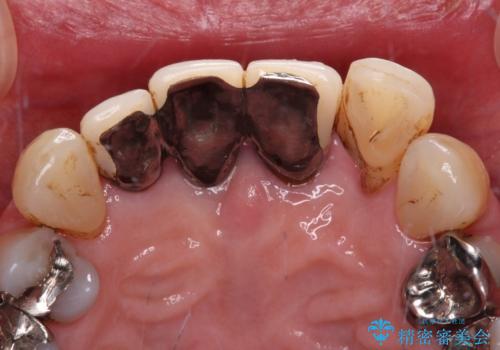

- 上顎前歯の違和感や不快感を気にして来院された患者様です。

現在のクラウンは金属の縁が見えており、歯と歯と歯肉の間に大きなスペースができていて、見た目も悪く、物が挟まったり話しにくかったりしていました。

また、前歯に抜歯が必要な歯があったため、抜歯をし、傷の治りを待ってオールセラミックブリッジにて補綴治療を行うこととしました。